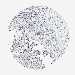

PANCREATIC CANCER - Protein expressioni

A mouse-over function shows sample information and annotation data. Click on an image to view it in a full screen mode. Samples can be filtered based on level of antibody staining by selecting one or several of the following categories: high, medium, low and not detected. The assay and annotation is described here.

Note that samples used for immunohistochemistry by the Human Protein Atlas do not correspond to samples in the TCGA dataset.

Antibody stainingi

Antibody staining in the annotated cell types in the current human tissue is reported as not detected, low, medium, or high, based on conventional immunohistochemistry profiling in selected tissues. This score is based on the combination of the staining intensity and fraction of stained cells.

Each image is clickable and will lead to virtual microscopy that enables deeper exploration of all samples and also displays staining intensity scores, fraction scores and subcellular localization as well as patient and tissue information for each sample.

Antibody HPA020391

Staining

High

Medium

Low

Not detected

Intensity

Strong

Moderate

Weak

Negative

Quantity

>75%

75%-25%

<25%

None

Location

Nuclear

Cytoplasmic/membranous

Cytoplasmic/membranous,nuclear

Adenocarcinoma, NOS